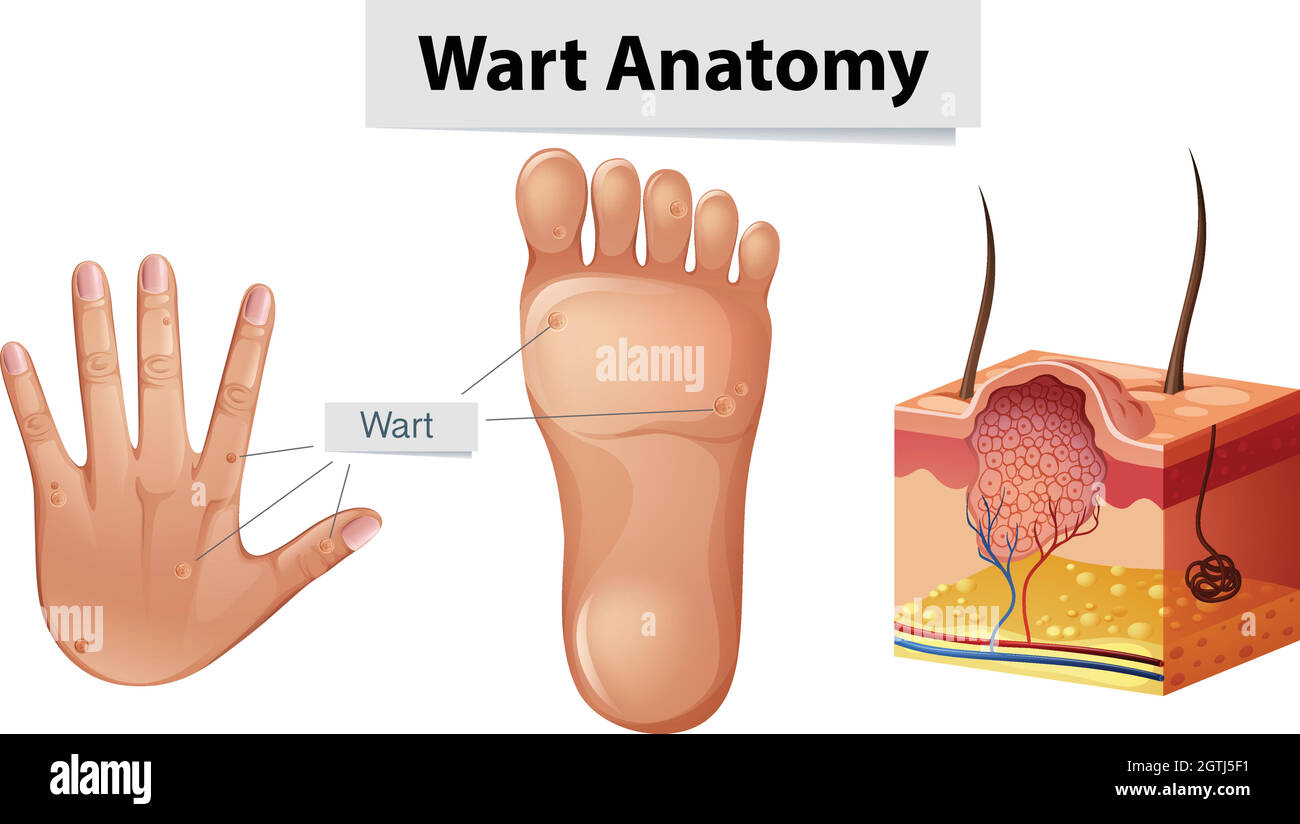

RF2ABM669–La médecine et les soins de l'illustre le tableau, les droits de l'anatomie du pied : Peau et tissus ectodermaux, os, muscles nerfs, vaisseaux sanguins

RF2H0E7GG–Maladie des bactéries des pieds causant une odeur comme un corps humain montrant les orteils avec une infection bactérienne danger comme symbole de maladie de peau comme un podiatrie.